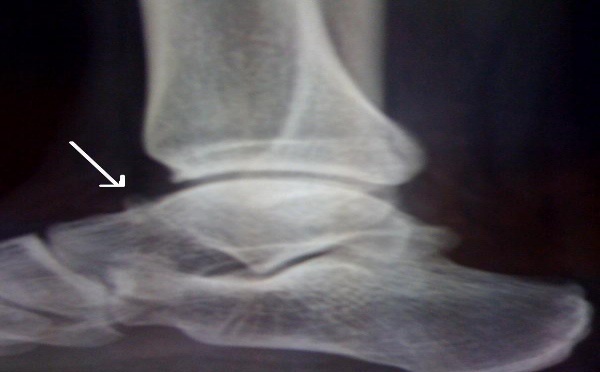

La cheville et le pied

Lésion de l’articulation talo-naviculaire

Une séquelle rare d’entorse de Chopart…